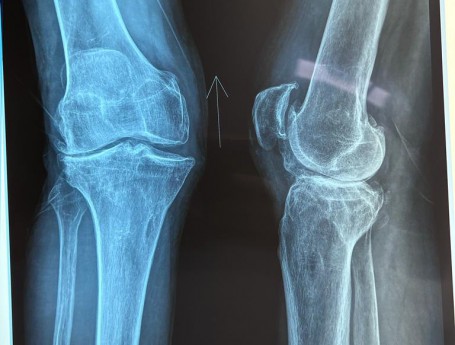

Knee Pain

Knee Exam

Total Knee Arthroplasty on a severe Genu Valgum